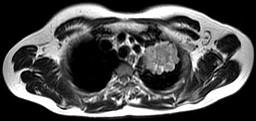

问题 男,68岁,声音嘶哑半个月,行MRI检查如图,其最可能的诊断为 ( )

选项 A.右上肺癌 B.左上肺结核球 C.左上肺炎性假瘤 D.左上肺癌 E.左上肺动静脉瘤

答案 D